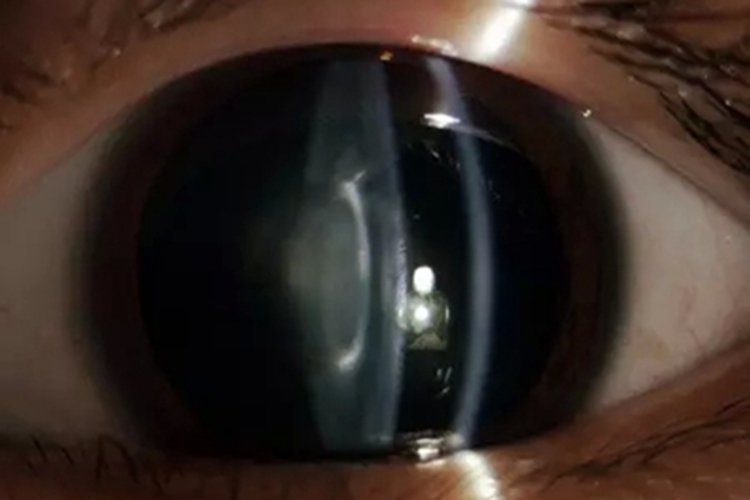

核性白内障

核性白内障临床可表现为眼睛的中央出现一大块白斑,几乎覆盖整个黑眼球,形状不规则,边缘不规则,这是患者晶状体混浊的外在表现。患者会因此出现视力下降、色觉改变等症状。